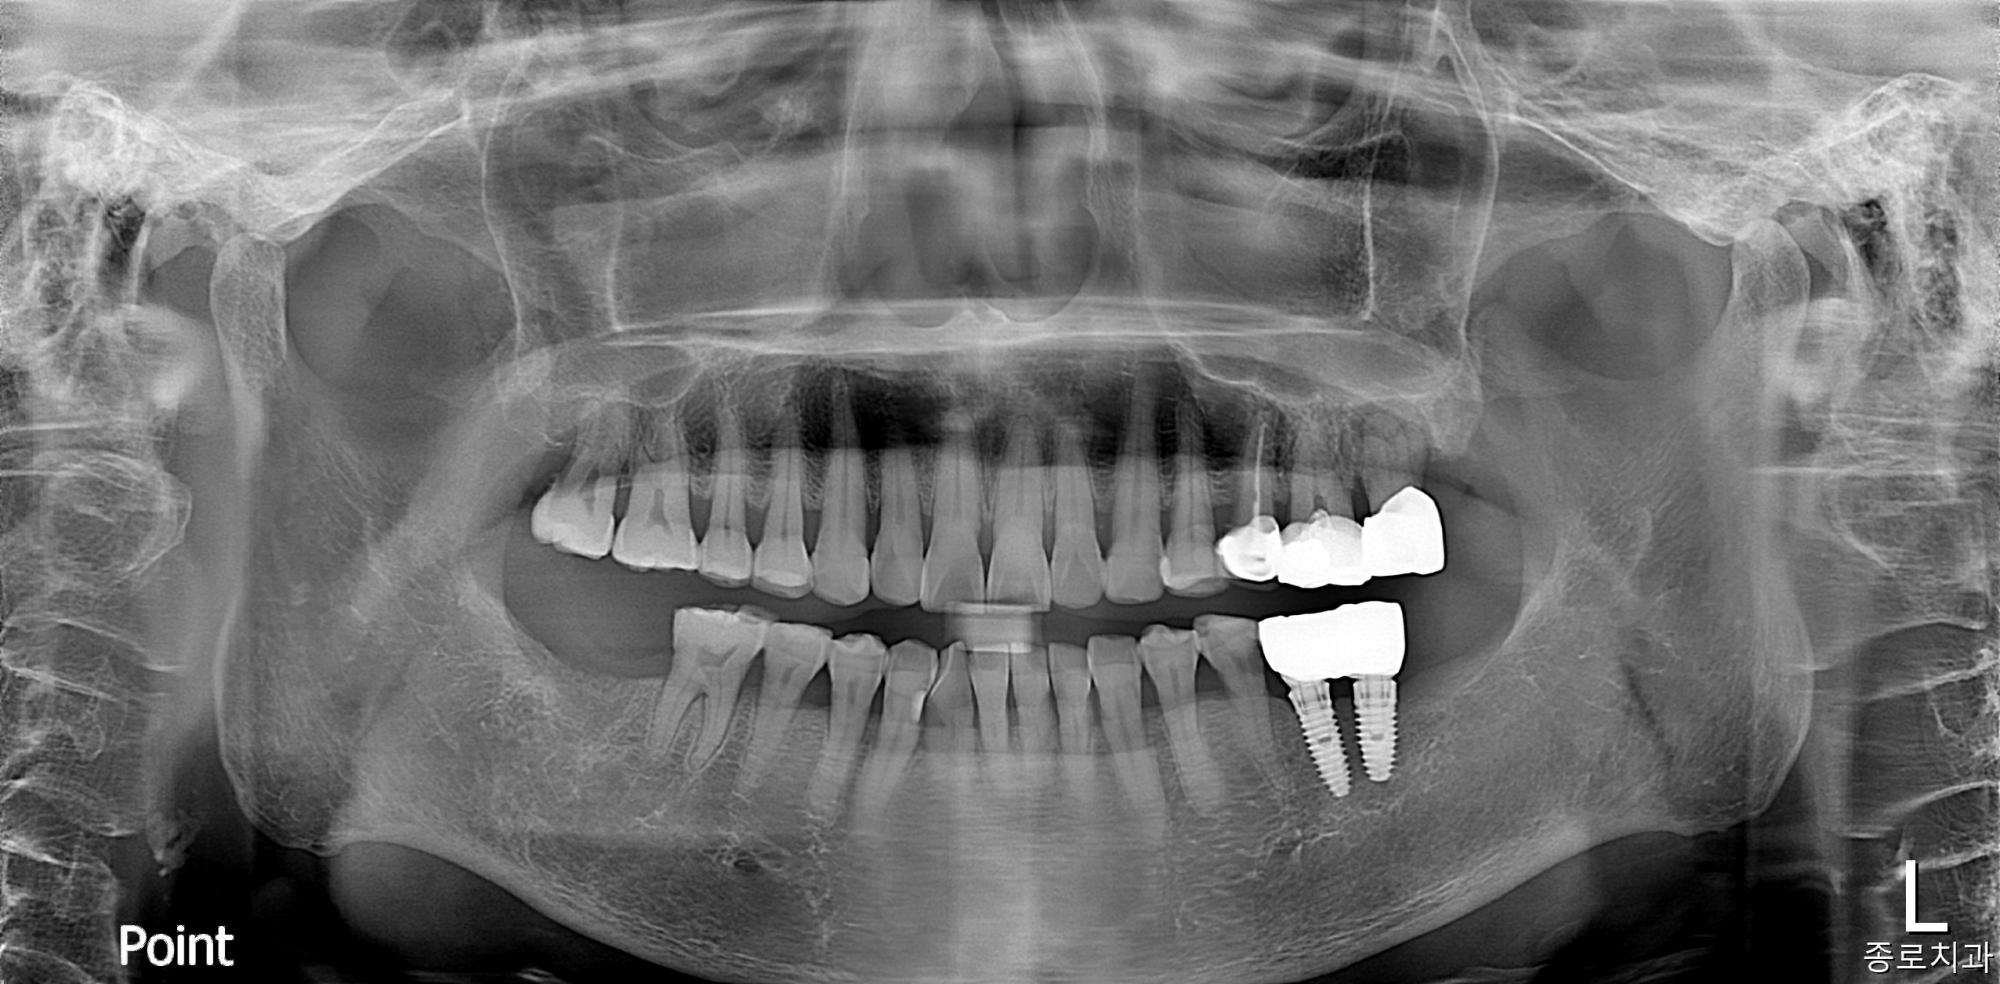

전/후 사진갤러리